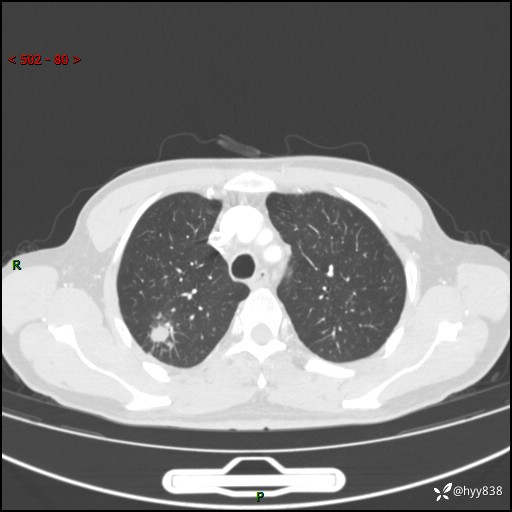

69岁/男,发现肺部病变6天。该有的征象都有,肉芽肿 VS 肿瘤,一念之间---(有结果)

主诉:发现肺部病变6天。

现病史:患者6天前于我院泌尿外科住院,住院期间行胸部CT检查,提示“肺部病变”,患者无畏寒、发热、盗汗、咳嗽、咳痰、咯血、胸痛、呼吸困难,无反酸、腹痛、腹泻、头痛、头晕等不适。未予特殊处理,现为进一步诊治,门诊以“肺肿物”收入我科。 患者本次起病以来,精神食欲尚可,大小便正常,体力及体重无明显变化。

胸部CT平扫+增强